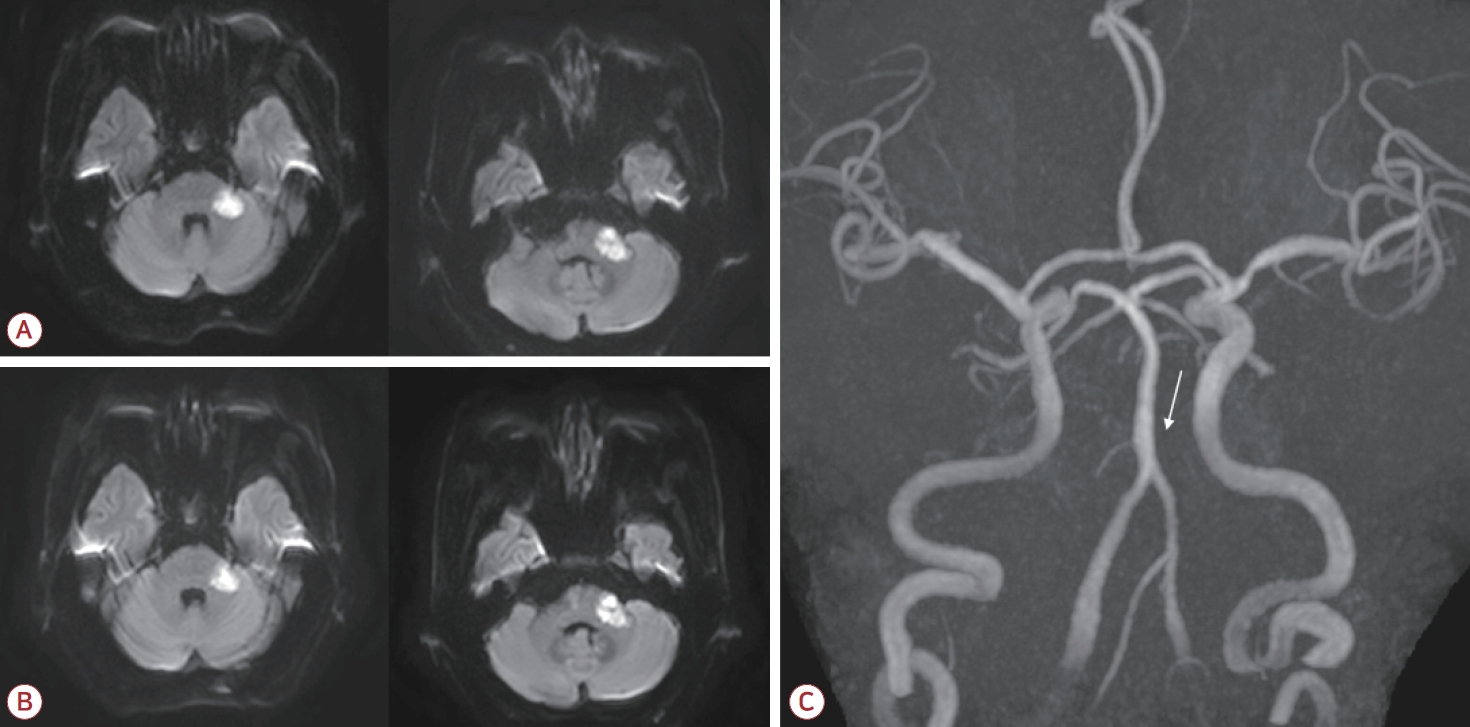

A 76-year-old male was admitted to our hospital due to the sudden onset of dizziness and disequilibrium 7 days previously. His neurological status had deteriorated, and he had been unable to walk independently for the past 5 days. The patient had a history of hypertension that had been managed with medication, and he had no known history of diabetes mellitus, cardiac disease, or previous stroke. In the initial neurological examination the patient was fully alert but had slight dysarthria. Extraocular movements were normal with the exception of gaze-evoked nystagmus being more severe on the left side. Sensations to light touch and pinprick were intact throughout the body, including the face. Despite the patient not complaining of any hearing disturbance, Weber and Rinne tests indicated sensorineural hearing loss on the left side. The muscle strength was normal but the patient displayed bilateral appendicular ataxia, which was more severe in the left limbs. His gait was unsteady and he was unable to walk in tandem. Diffusion-weighted imaging of the brain showed acute ischemic lesions in the left middle cerebellar peduncle and the left lateral pons corresponding to the territory of the AICA (Fig. 1-A). A focal chronic infarction was also observed in the right cerebellum. Magnetic resonance (MR) angiography revealed no abnormalities in the bilateral vertebral arteries or the basilar artery (BA), but there was a cut-off appearance of the left AICA where it originated from the BA (Fig. 1-C). Mild bilateral stenosis was also observed in the mid-M1 segments of the middle cerebral arteries. Hematological and cardiac investigations showed no abnormalities. Measuring the lipid profile revealed total cholesterol at 161 mg/dL, triglycerides at 201 mg/dL, high-density lipoprotein (HDL) cholesterol at 32 mg/dL, and low-density lipoprotein (LDL) cholesterol at 110 mg/dL.

High-intensity statin and dual antiplatelet therapy (aspirin and clopidogrel) was initiated for secondary stroke prevention due to the presence of atherosclerotic risk factors. However, at 3 days after the admission (corresponding to 10 days after the initial onset of stroke symptoms) the patient developed new-onset left facial weakness affecting both the upper and lower face. The weakness had a severity of House-Brackmann grade IV, characterized by an inability to wrinkle the left forehead, incomplete closure of the left eye, and mouth asymmetry (Fig. 2). Ocular movements remained intact. A nerve conduction study of the facial nerves was performed. Following stimulation of the left facial nerve, the compound motor action potentials were 31% lower in the left orbicularis oris and orbicularis oculi than on the right side. After stimulating the left supraorbital nerve, the blink reflex test revealed that ipsilateral R1 and R2 responses were absent while the contralateral R2 response was normal, confirming the presence of left facial neuropathy. The brainstem auditory evoked potential did not respond to the left-ear stimulation. Follow-up magnetic resonance imaging (MRI) of the brain was performed to evaluate the new-onset facial palsy, which revealed maturation of the existing ischemic lesions involving the left middle cerebellar peduncle and the lateral pons (Fig. 1-B). Importantly, no new infarction or significant expansion was detected that could explain the delayed facial palsy. The patient was managed conservatively without corticosteroid therapy, and the left facial palsy improved 1 month after its onset.

Figure 1.

(A) Diffusion-weighted imaging of the brain showed high signal intensities in the left middle cerebellar peduncle and the lateral pontine area. (B) Follow-up imaging performed 6 days later demonstrated maturation of the ischemic lesions, with no significant expansion. (C) Magnetic resonance angiography of the brain indicated nonvisualization of the left AICA where it originated from the basilar artery (white arrow). AICA; anterior inferior cerebellar artery.